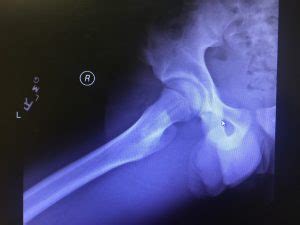

Lesser Trochanter Fracture Treatment / Anteroposterior radiograph demonstrating left hip lesser ... - This injury is a result of a sudden forceful contraction of the iliopsoas tendon.

Hip fractures, especially fractures of the femoral head, are often associated with a hip dislocation. The goal of treatment for this particular type of fracture should be to restore the patient to his or her. Anterior greater trochanter posterior greater trochanter. An intertrochanteric fracture occurs between the greater and lesser trochanters. Greater and lesser trochanter fracture causes & treatment. The lesser trochanter projects from the base of the. An initial manifestation of metastatic malignant disease. The iliopsoas attaches to the lesser trochanter, resulting in internal rotation and external rotation with fractures. In all intertrochanteric fractures, if the fracture line extends distally, a long nail will be necessary. This injury is caused by severe impact, usually in context of contact sports and following a forceful and sudden muscle contraction of the iliopsoas with avulsion fracture of the. An intertrochanteric fracture occurs along a line that is located between the greater and lesser trochanters. The lesser trochanter of the femur is a conical eminence, which varies in size in different species. Avulsion fractures of the lesser trochanter in adolescents are uncommon.

Nonoperative treatment demonstrated good clinical course. This new sporting activity involves kicking the ball continuously, typically with both the hip and the knee in flexion. The treatment for this type of fracture remains challenging as the disease is usually discovered at final stage. Avulsion fractures of the lesser trochanter in adolescents are rare. In the intramedullary nail shown here a spiral blade device is used to. This injury is a result of a sudden forceful contraction of the iliopsoas tendon. Lesser trochanter fracture anatomy • lesser trochanter is attachment site for iliopsoas mechanism • fracture may be due to avulsion • in the absence of injury, isolated lesser trochanter fracture is highly suspicious for an underlying malignancy imaging • obtain mri to assess extent of. The iliopsoas attaches to the lesser trochanter, resulting in internal rotation and external rotation with fractures. In all intertrochanteric fractures, if the fracture line extends distally, a long nail will be necessary. The goal of treatment for this particular type of fracture should be to restore the patient to his or her. Although the treatment of apophyseal injuries rarely requires surgical intervention, 3 other injury patterns may cause hip pain. In case of primary tumors with clear. We report the case of a skeletally immature freestyle footballer who presented with avulsion fracture of the lesser trochanter.